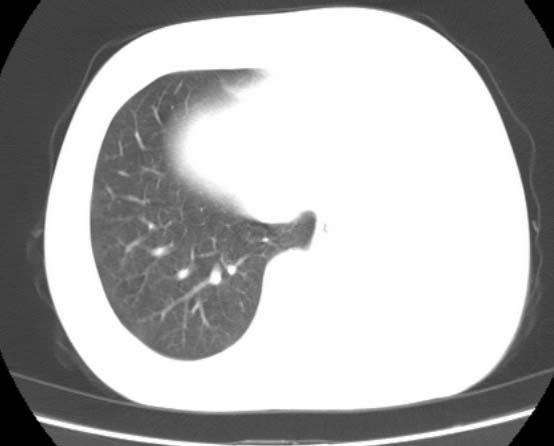

女  20岁。一月前咳血,诊“肺结核”抗痨治疗一月后,咳血停止,现复查。病人精神好。前后ct片对比未见明显变化。既往体检“正常”

1)考虑左肺结核并肺不张、支气管扩张。2)纵隔疝。

考虑左肺结核,左肺毁损,纵膈左偏,既往体检正常不可靠,tb一个月也不会这个样子的,有钙化,应该病程较长,冰冻三尺非一日之寒!

左肺发育不全。

考虑左肺结核,左肺毁损,纵膈左偏,既往体检正常不可靠,tb一个月也不会这个样子的,有钙化,应该病程较长,冰冻三尺非一日之寒

结核,左肺毁损。